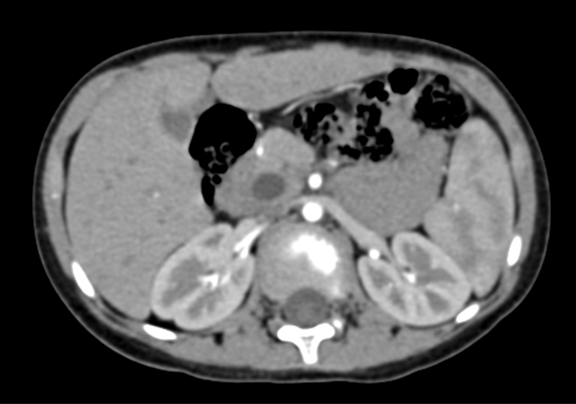

上腹部CT 动态增强:1. 肝内部分胆管-肝门部胆管-胆总管扩张,符合先天性胆管扩张症2. 胆总管下段腔内结节状略高密度影,伪影?结石?3. 胆囊壁略厚,提示胆囊炎可能。

术前CT检查:

动脉期

静脉期

平衡期